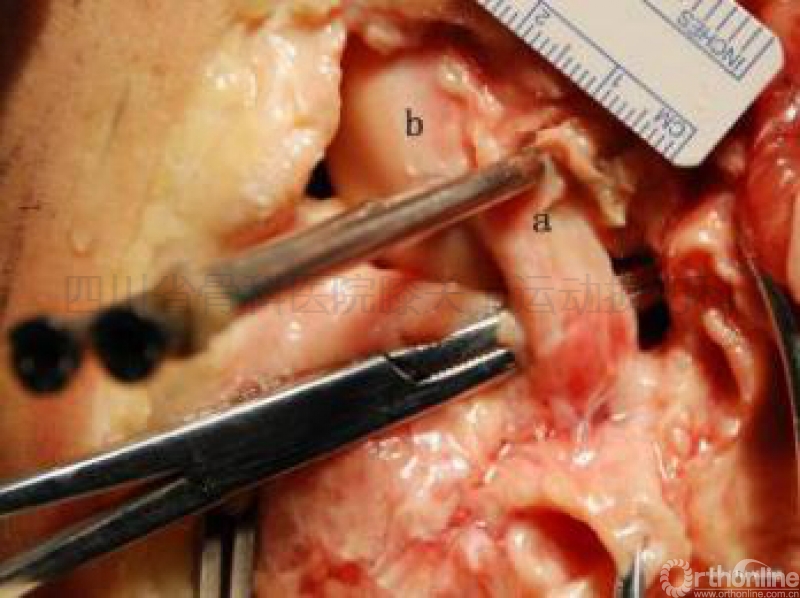

在2011年,作者按照PabloEduardo Gelber等设定的试验要求,经尸体试验发现:RigidFix横穿钉在一些标本会从外侧副韧带与腘肌腱之间的间隙穿过(图示二),

图示二尸体试验显示RigidFix双鞘管在经前内入口安全区的击入点。

a点标示为腘肌腱;b点标示为外侧副韧带;c点标示为腓肠肌外侧头。

幸运的是,鞘管刚好从三者之间的间隙穿过。

但也有标本被发现横穿钉穿过了腘肌腱及外侧副韧带,甚至穿到了股骨外髁边缘的关节软骨上(图示三)。

图示三尸体试验显示RigidFix双鞘管在经前内入口安全区的击入点。

a点标示为腘肌腱;b点标示为股骨外髁下缘的关节软骨。

不幸的是,一个鞘管穿过了腘肌腱,一个穿在了关节软骨上。